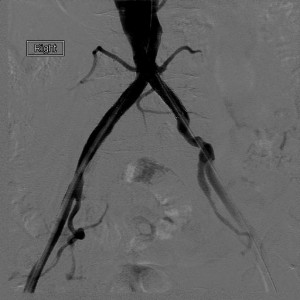

small aorta syndrome post stent angiography

Small aorta syndrome post stent as seen on angiography

Earlier reports also exist of small aorta syndrome causing intermittent claudication. Obviously it is an uncommon cause of non-atherosclerotic peripheral artery disease. It should be noted, though, that often women are found to have small aortas and iliac arteries, but they do not have symptoms. Obviously these women do not need to be treated.